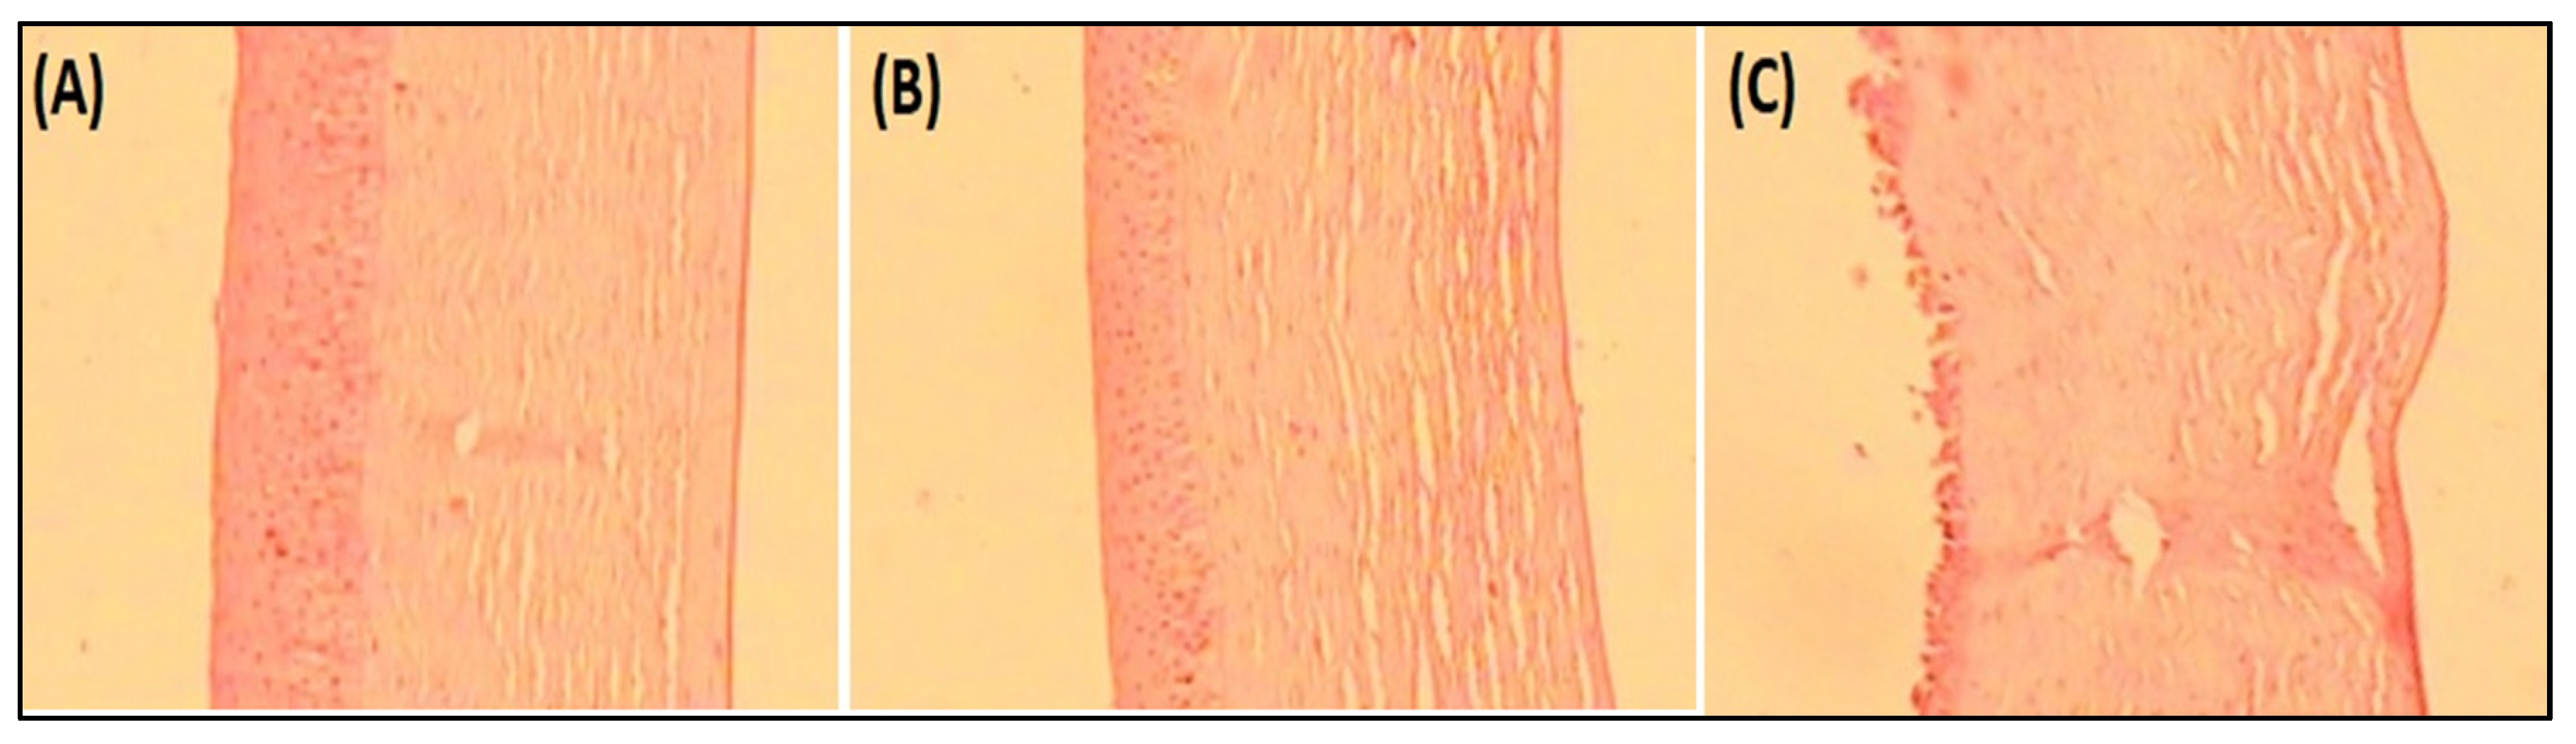

3.5.9. Histopathological Examination

This study was carried out to observe any alteration in the internal corneal structure with the tested samples compared with the positive control. The tissue was treated similar to the ex vivo corneal permeation study for EM-NLCs-opt-IG4, negative control (0.9% NaCl) and positive control (1% w/v; SLS). The cornea was collected and stored in formalin solution (0.8%, v/v). The cornea was fixed into the solid block using paraffin after dehydration with alcohol. The microtome cutter was used to cut the cross-section and further stained with haematoxylin and eosin dye. The image was captured with a Motic digital optical microscope at 40× magnification.

4.8.6. Histopathological Examination

Histopathology study on goat cornea showed the cornea treated with EM-NLCs-opt-IG4 and negative control (0.9% NaCl) had typical corneal structures (Figure 7A,B), and cells retained their normal morphology. It was concluded that, upon treatment, the epidermal layer remains unchanged. The cornea treated with the positive control (1% w/v; SLS) showed damage to the destruction of corneal epithelial cells (Figure 7C). Finally, based on histopathology study, it was established that the EM-NLCs-opt-IG4 was found safe for ocular delivery.

Figure 7.

Histopathological image of (A). EM-NLCs-opt-IG4, (B). Negative control (0.9% NaCl) and (C). Positive control as SLS (1% w/v).